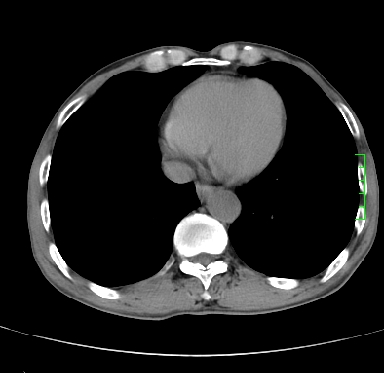

m,73y。膝关节疼痛伴双下肢水肿。入院常规胸片发现结节灶。增强为静脉期。

指套征,强化明显,近侧肺组织局限性肺气肿,考虑支气管类癌,慢支、肺气肿、双上陈旧性tb、冠脉钙化。

1)考虑右肺下叶周围型肺癌。2)右肺上叶及左肺感染性病变(结核可能)。3)肺气肿。4)冠状动脉钙化。